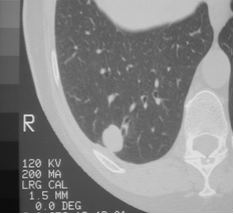

Smooth

(but 21% of malignant

nodules are smooth,

esp. metastases)